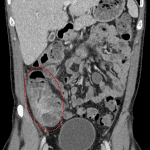

Indication: Right lower quadrant pain, neutropenic fever

- Marked mural thickening of the cecum and ascending colon with surrounding fat stranding

- Small amount of free fluid in the right paracolic gutter without loculated collection or free air

- Typhlitis

Marked inflammation of the cecum and proximal ascending colon, concerning for typhlitis in this neutropenic patient. No evidence of abscess, perforation, or ischemia.

Normal appendix.